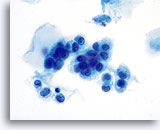

Benign Appearing Endometrial Cells

Endometrial cells may display a wide range of nuclear and cytoplasmic size, as well as architectural configuration. Endometrial cell groups tend to round up in ThinPrep solution. The nuclei are well preserved and appear crisp with distinct, active chromatin; chromocenters are frequently noted.

Bethesda 2014 recommends the reporting of benign appearing exfoliated endometrial cells in women age 45 and above, regardless of clinical history. The general categorization “Other” was included in the Bethesda 2001 lexicon for this purpose. Histiocytes, stromal cells and abraded endometrial cells do not have the same significance as exfoliated endometrial cells and should not be considered in the same context. While most often benign, identification of endometrial cells, particularly if not associated with menses or after menopause, may indicate risk for an endometrial abnormality.